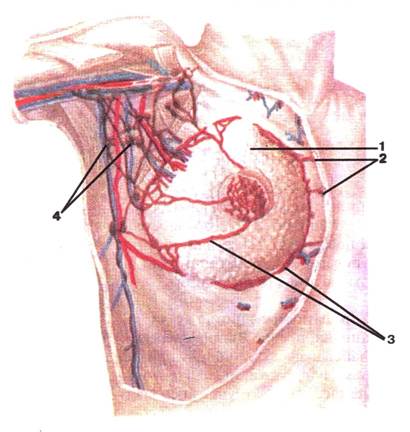

Малюнок А. 6 – Лімфатичні судини та вузли грудної залози.

Вигляд спереду:

1 -mamma; 2 -nodi lymphatici parasternales; 3 -vas lymphaticum; 4 -nodi lymphatici axillares